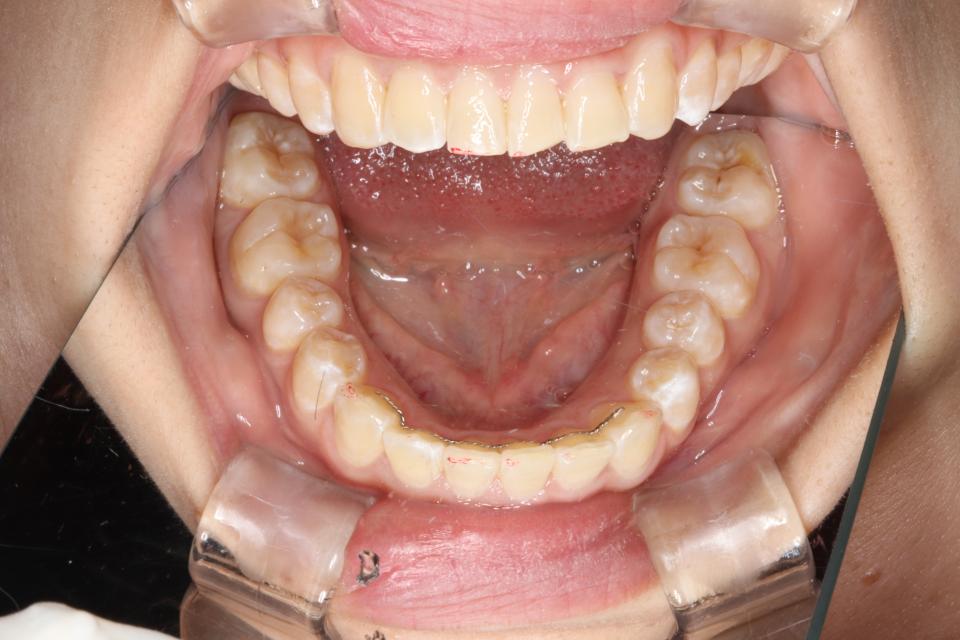

がたがた(叢生)のワイヤー矯正治療例(抜歯あり)

矯正治療後

20代女性の患者さんです。

下の前歯のがたつきを気にして来院されました。

上左右4番抜歯をして、上下の歯にワイヤー(マルチブラケット装置)をつけて治療しました。

きれいに並びきるために歯のやすりがけ(IPR)も行っています。

歯並びを並べる治療は終わり、現在は前歯の裏側にワイヤーをつけ、それと同時に

取り外しのできる装置をはめることで後戻りの防止をして、